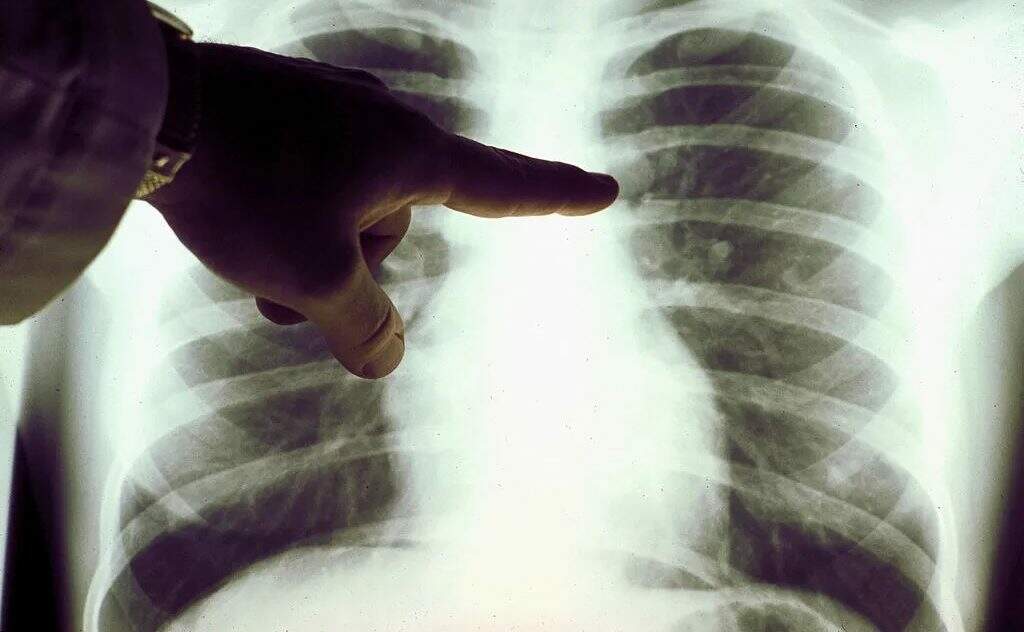

Um dos obstáculos para entender melhor essa tendência é o avanço no diagnóstico, que também contribui para mais detecção da doença.

Um dos obstáculos para entender melhor essa tendência é o avanço no diagnóstico, que também contribui para mais detecção da doença. (Foto: Reprodução)

Há indícios de que a incidência absoluta de câncer de pulmão em nunca-fumantes vem aumentando. Um dos obstáculos para entender melhor essa tendência é o avanço no diagnóstico, que também contribui para mais detecção da doença.